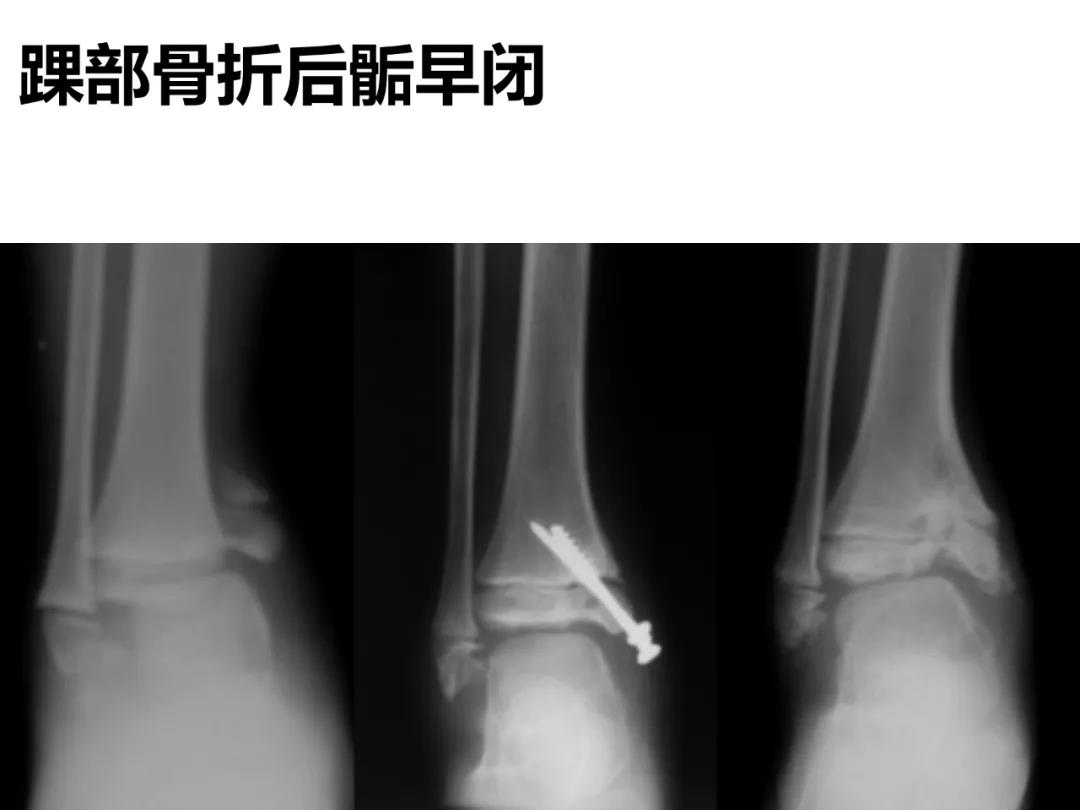

小儿骨科X线片汇总,临床读片宝典!